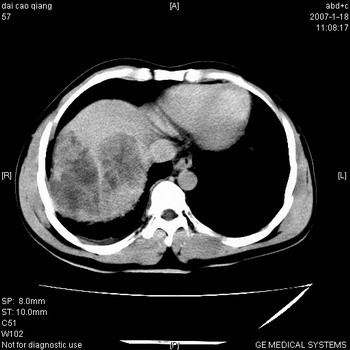

肝右叶巨块型肝癌,伴癌栓形成.

符合巨块型肝癌表现:

1、平扫低密度,增强后表现为快进快出。

2、动脉期可见迂曲的动脉供血血管

3、并可见门静脉右支癌栓形成

4、可见假包膜

5、腹主动脉旁结节影,考虑肿大淋巴结。

典型的肝右叶巨块型肝癌破裂、门脉瘤栓形成。

肝右叶巨大不均匀低密度肿块,前缘有假包膜,增强明显的呈快进快出表现,门脉右支有癌栓,病人虽然年轻但还是首先考虑肝右叶巨块形肝癌,病人血象高只能说有合并感染。不支持肝脓肿。